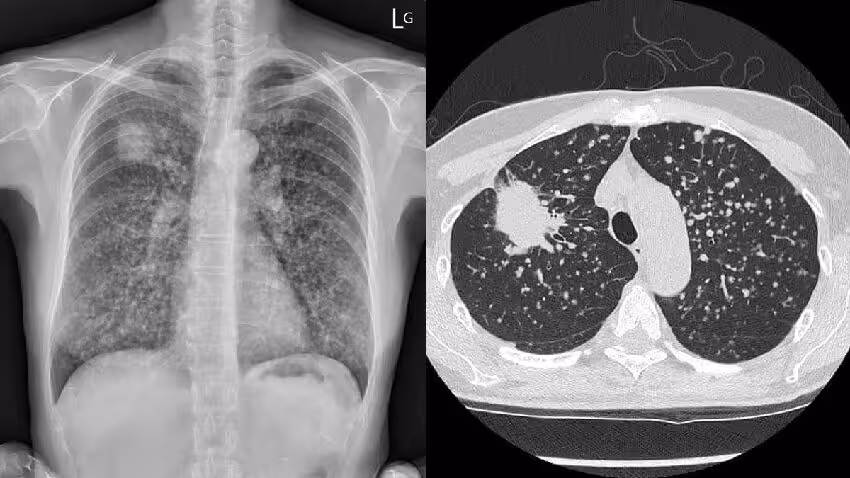

許多醫護朋友看個案年輕又咳嗽1個月,馬上懷疑是否有抽煙:「這個GGO (毛玻璃樣病灶,Ground Glass Opacity) 好像沒有很明顯?

煙抽很久嗎」、「請問他有抽煙嗎」,蘇醫師指出男病患雖年輕,但煙齡已經有2、30年了。

其他網友也搖頭:「抽煙就不意外了,我媽沒抽煙也得,還過世了」、「我當clerk (見習醫生) 的時候 (25年前了) ,老師就教感冒咳嗽咳超過一個月的要照X光,懷疑惡性」。